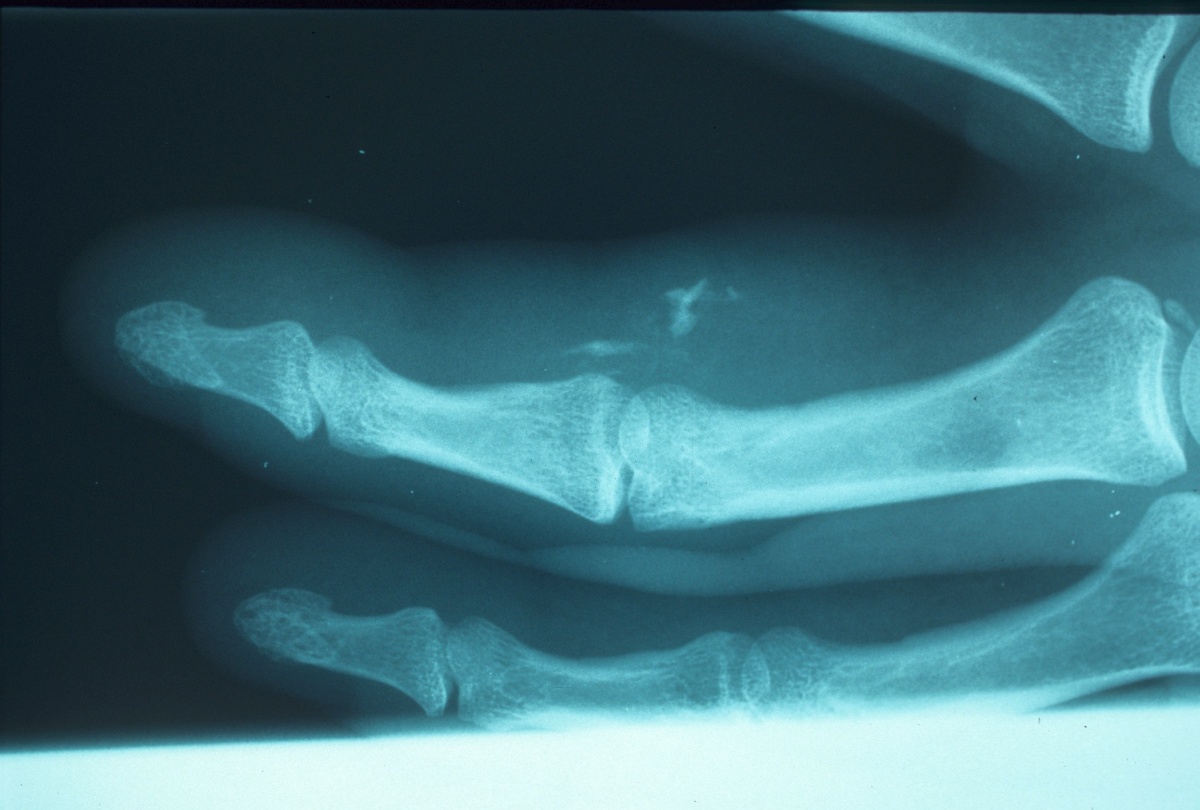

Case 2. Patient presented with pain, stiffness and a wound four days after pressure injection injury with red latex enamel.

Minimal pigmented debris.

Contamination extended the length of the finger and involved the flexor tendon sheath. The A2 and a portion of the A4 pulleys were preserved. Stained tissue was excized and neurovascular bundles were preserved. The proximal flap was advanced to cover the excision defect with a Z-plasty, shown in a later image.